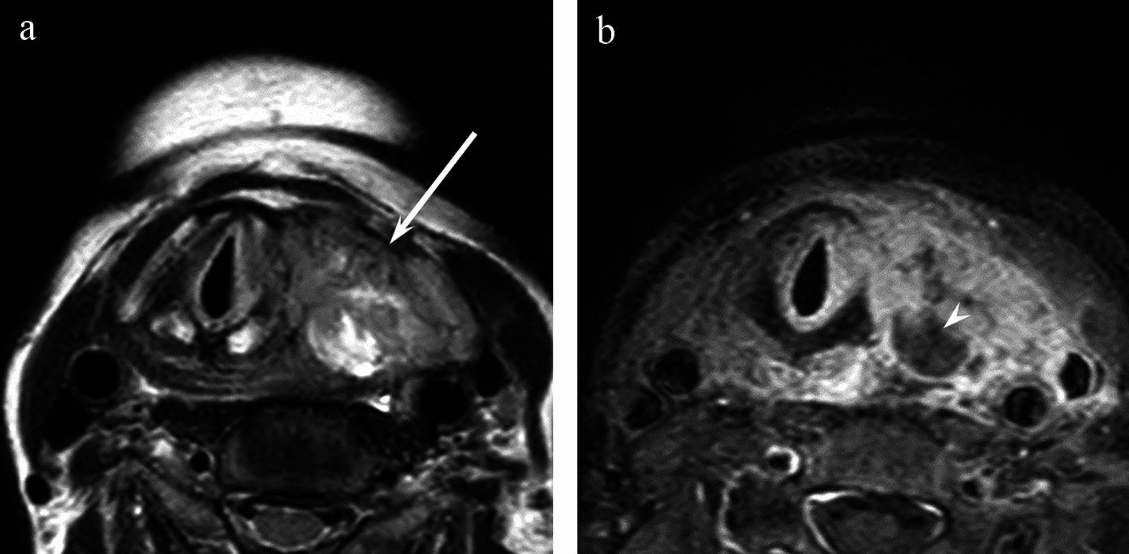

MRI accurately detects extrathyroidal extension, which means the tumour has spread beyond the thyroid gland itself into surrounding tissues like muscle or fat1,15. This finding signifies a more advanced or aggressive disease and affects treatment plans significantly.

MRI can clarify whether cancer is invading key structures near the thyroid, such as the windpipe, nerves, and major blood vessels, which is critical for surgical planning and prognosis1,16.

The solid components of anaplastic thyroid carcinoma frequently show hyperintensity on T2-weighted images compared to the spinal cord17. It also often presents with ill-defined margins and shows a higher incidence of extension out of the thyroid, tracheal, and oesophageal invasion, vascular invasion, and venous thrombosis, reflecting their aggressive nature.